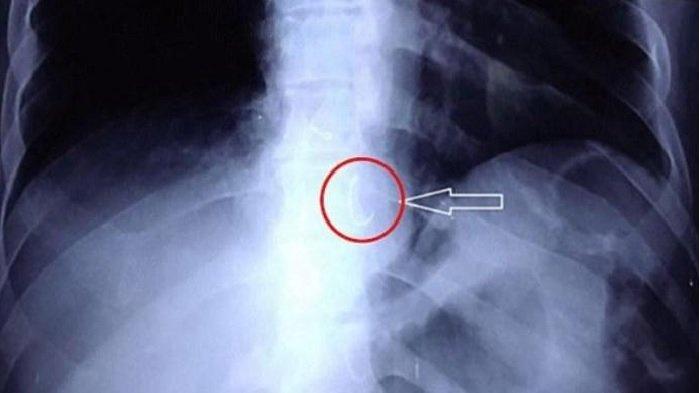

Akhirnya Gigi Palsu 15 Tahun di Paru-paru Warga Aceh Bisa Dikeluarkan, Awalnya Tertelan saat Tidur

Setelah 15 tahun gigi palsu berada di paru-paru, dokter dokter Rumah Sakit Umum Daerah Zainoel Abidin ( RSUDZA) Banda akhirnya berhasil mengeluarkannya.

Saking lamanya, gigi palsu itu sudah menempel dengan paru-paru pasien tersebut.

Pada pasien ini, bronkoskopi dilakukan sebagai tindakan untuk mengeluarkan gigi palsu.

Karena letak gigi palsu yang terlalu dalam, tindakan pada pasien ini memakan waktu sampai 1 jam 30 menit.

Kasus ini dirasa sulit karena benda asing atau gigi palsu sudah lengket di paru sebelah kiri.